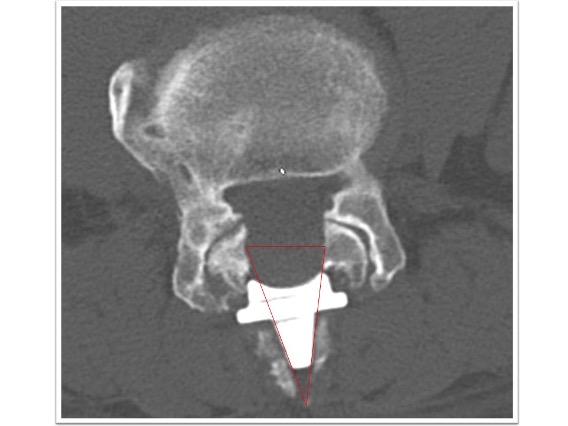

頚椎椎弓形成術実例(*患者様の許可を得て掲載しています)

頚椎症性脊髄症

上肢の運動障害、歩行障害の患者様に対して頚椎椎弓形成術を実施。術後MRI画像で頚髄の圧迫が解除され頚髄前後にスペースが生まれています(図赤丸)。また、CT画像では術前後の比較で脊柱管の前後幅が約1.5倍以上に拡大していることが確認できます(図青矢印)。術後は歩行安定し、上肢運動も改善しています。